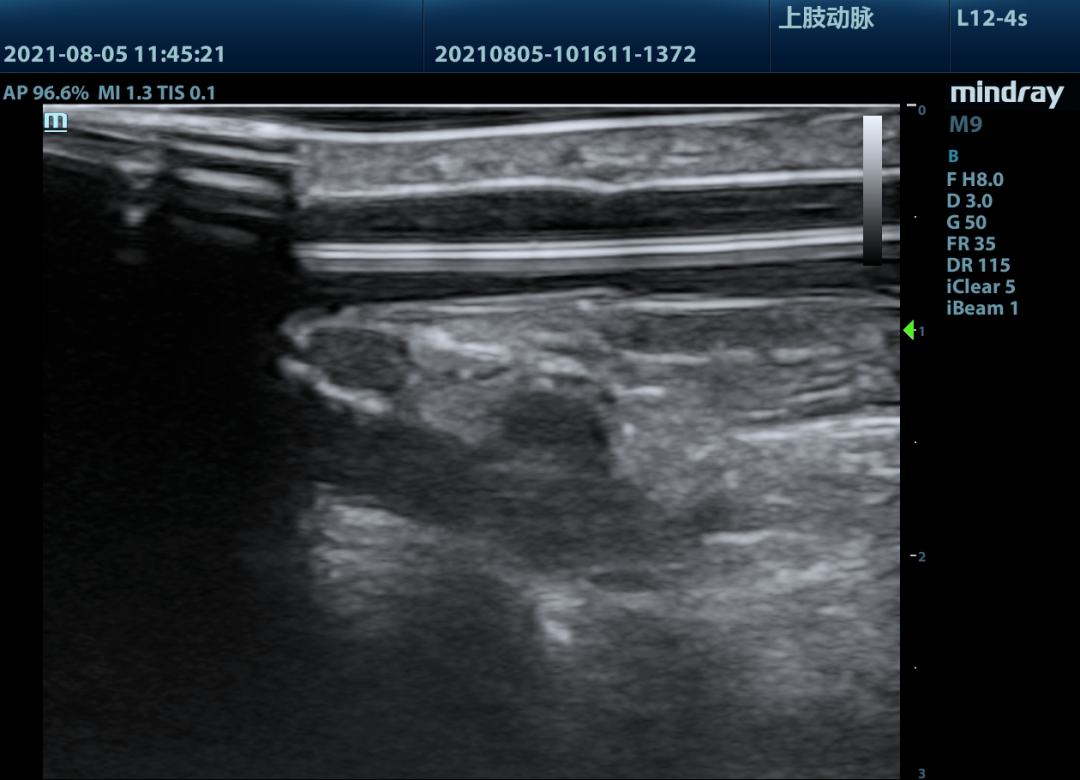

▲球囊继续加压,血管狭窄部出现双凹征逐渐消失

超声实时观察球囊扩张状态,直至球囊压迹消失,最后超声显示狭窄段血管完全再通,手术取得成功。